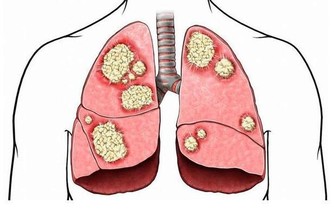

腳因為與心臟距離最遠,因此,血從心臟流到腳尖的過程也較長,很容易出現末梢迴圈障礙,導至供血不足;一些新陳代謝的廢物和各種毒素可能在足部積存下來,產生某種毒素,引起關節炎和一些器官的病變。 古人經常泡腳,用手按摩自己的腳心,天天散步,就是把氣血引到腳上去,只要新鮮的血液能引到腳上,令到氣血暢通,便可帶走在足部積存的代謝後廢物,運到腎臟處理後排出體外。 下肢血液回流心臟時,除胸腔吸氣運動產生的胸腔負壓和心臟舒張期產生的負壓吸引等作用外,主要依靠下肢肌肉在運動時的肌肉擠壓作用,特別是小腿肌肉(腓腸肌和比目魚肌是主要的「肌肉泵」)的擠壓作用,並藉助於靜脈瓣膜的單向開放功能,使靜脈血由遠端向近端、由淺靜脈向深靜脈流動,最後回流到心臟;我們把小腿肌肉的擠壓作用稱作「肌肉泵」作用,亦被稱為「第二心臟」。 下肢血液迴圈功能不佳,可影響人體各個器管的生理功能,導致各種疾病的發生,由此可以看出離心臟最遠的腳部肌肉的重要性。 雙腳的血液迴圈順暢,將促使全身的血液大循環亦處於良好狀態,你就可以延緩衰老。